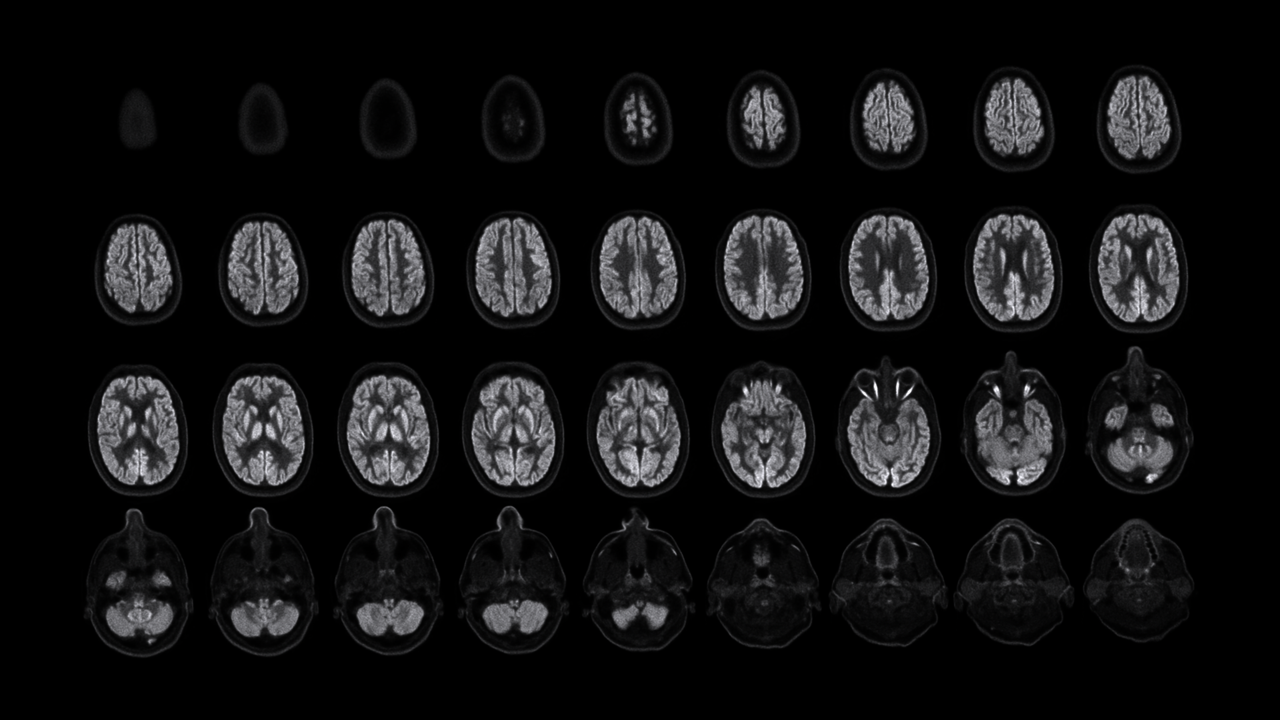

NeuroExplorer (NX) 产出到从头顶到肩部区域的完整图像